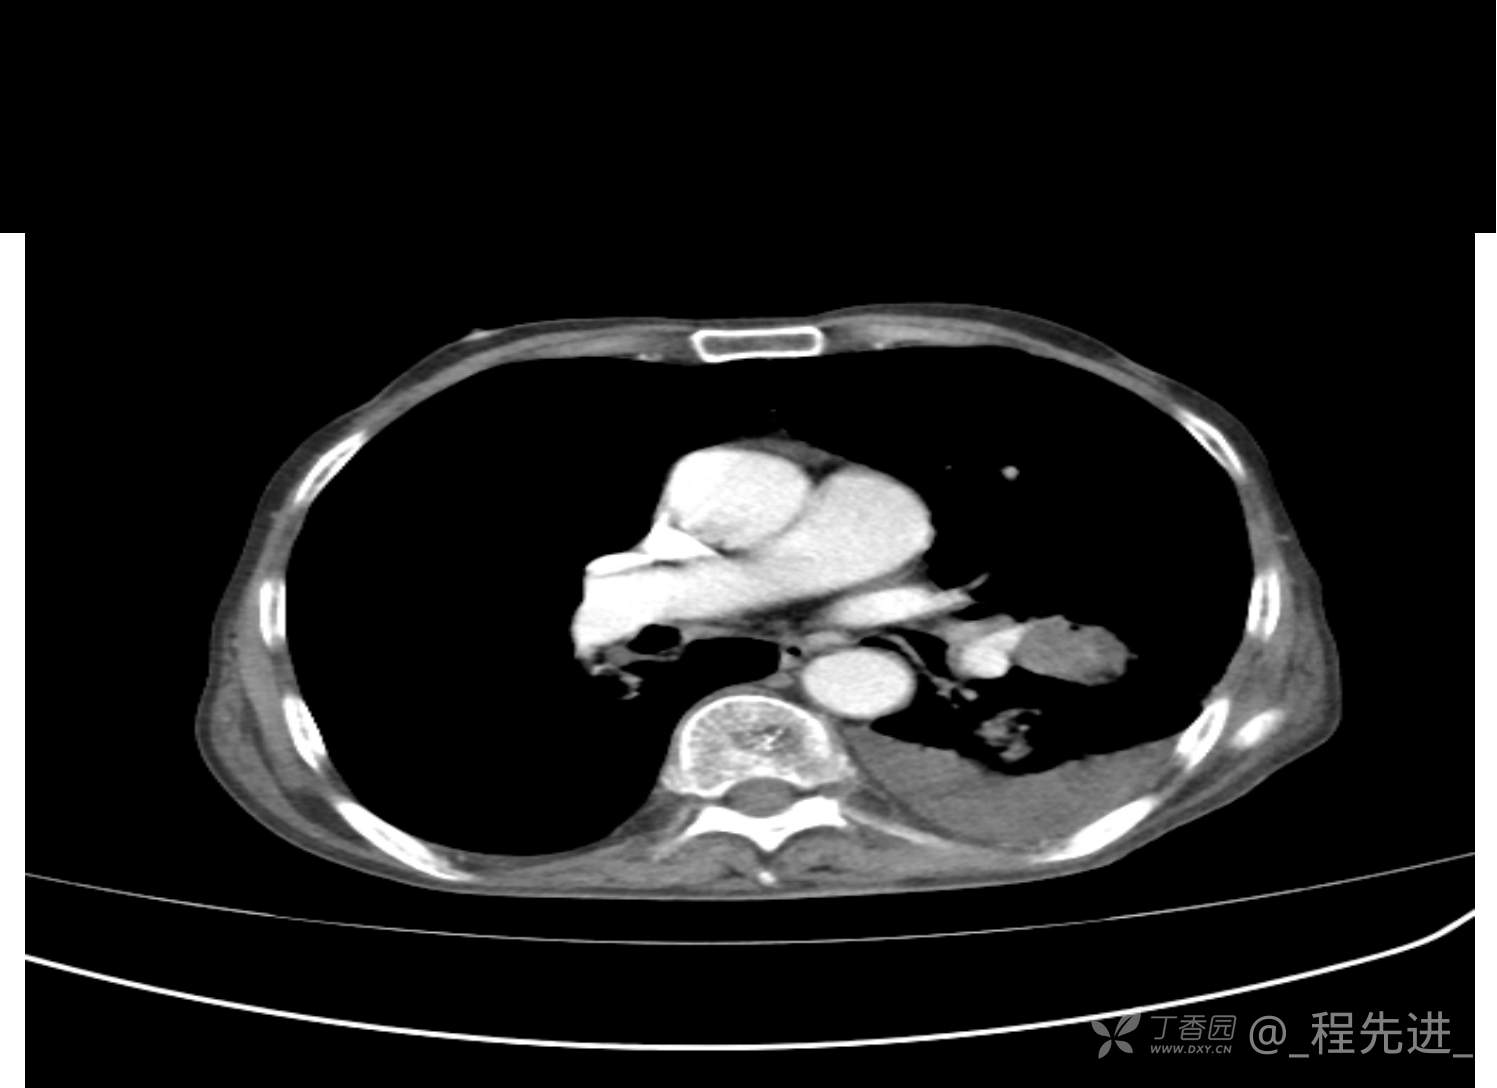

患者性别:男

患者年龄:81岁

简要病史:反复咳嗽、咳痰20余年,加重1周。两肺呼吸音低,可闻及散在干湿啰音。